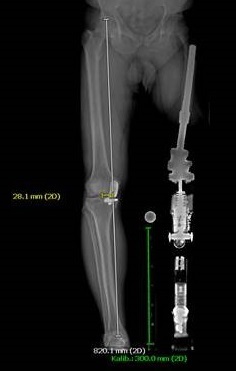

Endo Exo Prothesenversorgung

Links: Röntgenaufnahme Femurknochen

Rechts: Röntgenaufnahme Endo Exo Versorgung